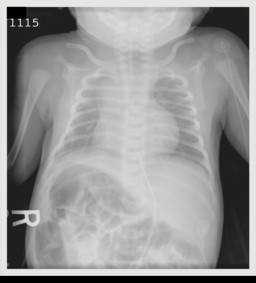

En los individuos con dextrocardia, que es una de las formas más "comunes" (comunes entre comillas por sigue siendo una enfermedad muy rara) de heterotaxia, el proceso de formación del corazón no ocurre adecuadamente provocando un desorden de lateralidad. Esto usualmente resulta en una enfermedad cardíaca compleja debido a que las cámaras izquierda o derecha suelen estar mal alineadas con las entradas y salidas de sangre normales (arterias y venas)).

La disposición normal del corazón y de los órganos se llama situs solitus Aunque hay algo de confusión en la bibliografía, se denomina situs inversus a una inversión perfecta del situs solitus, con el corazón hacia la derecha. Cualquier disposición diferente se denomina heterotaxia o situs ambiguus. La incidencia de situs inversus se estima que es de 1 en 10.000 nacimientos. La incidencia de heterotaxia es generalmente mucho menor y se suele acompañar de malformaciones cardiovasculares complejas.